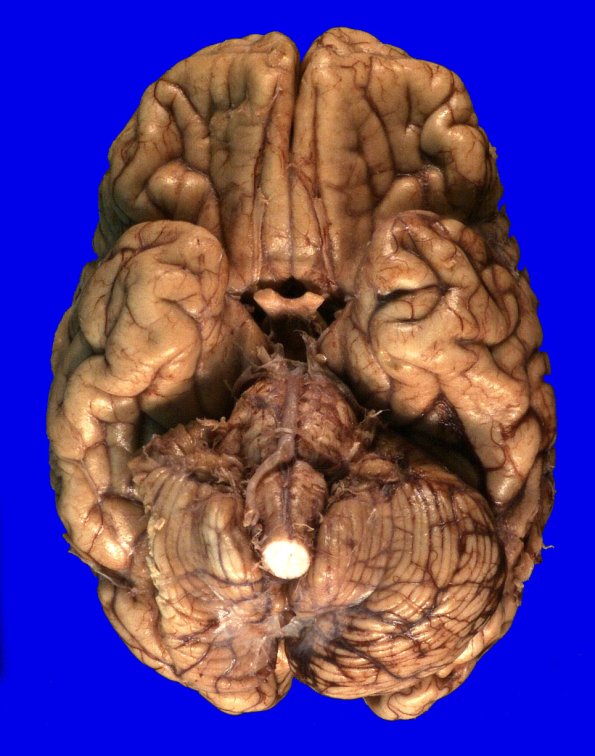

There was mild atrophy of the cerebral hemispheres with mild atrophy of the cerebellum seen in the ventral view.